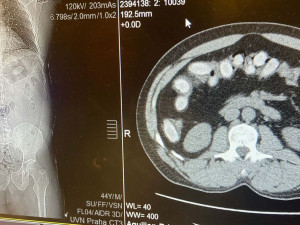

„Pětačtyřicetiletý cizinec cestoval linkovým autobusem na trase Brusel – Praha, přičemž cílovou destinací mělo být Rakousko. Při celní kontrole na něj pozitivně reagoval služební pes vycvičený na vyhledávání drog, označil ho a muž byl pro podezření přepraven do zdravotnického zařízení. Následné rentgenové vyšetření prokázalo výskyt cizích předmětů v tělních dutinách cestujícího a laboratorní rozbory potvrdily podezření celníků, že se jedná o kokain,“ informovala Hana Prudičová, mluvčí Generálního ředitelství cel.